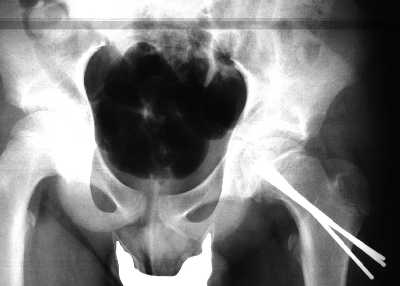

Il quadro, naturalmente, non migliora: I. continua a zoppicare, la coscia appare flessa e extraruotata. Una nuova lastra dimostra un notevole peggioramento del quadro radiologico (fig 1) con notevole risalita della testa femorale.

fig.1

Si impone un intervento chirurgico, di fissazione della testa al collo femorale.